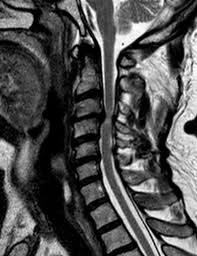

Es el desplazamiento de una porción del disco intervertebral cervical; la cual puede llegar a producir dolor y/o compresión de raíces nerviosas pudiendo provocar una lesión neurológica.